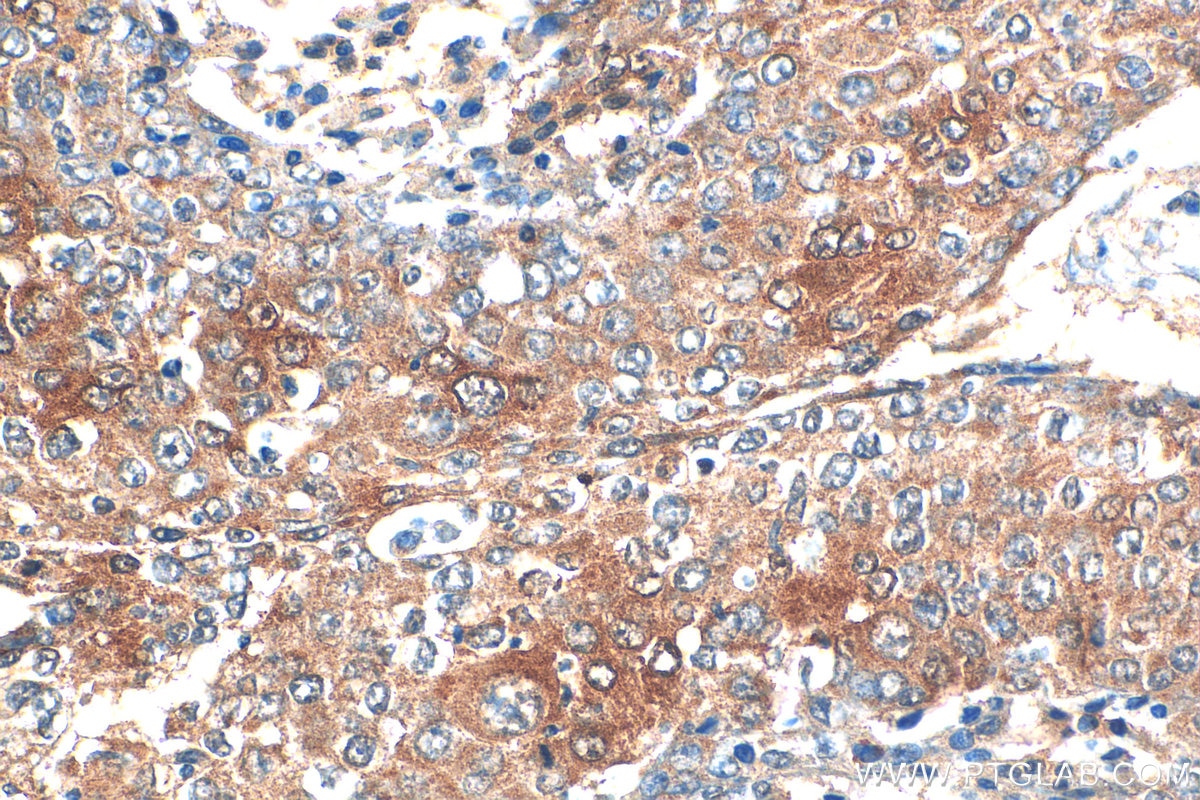

| Positive IHC detected in | human lung cancer tissue Note: suggested antigen retrieval with TE buffer pH 9.0; (*) Alternatively, antigen retrieval may be performed with citrate buffer pH 6.0 |

| Immunohistochemistry (IHC) | IHC : 1:50-1:500 |